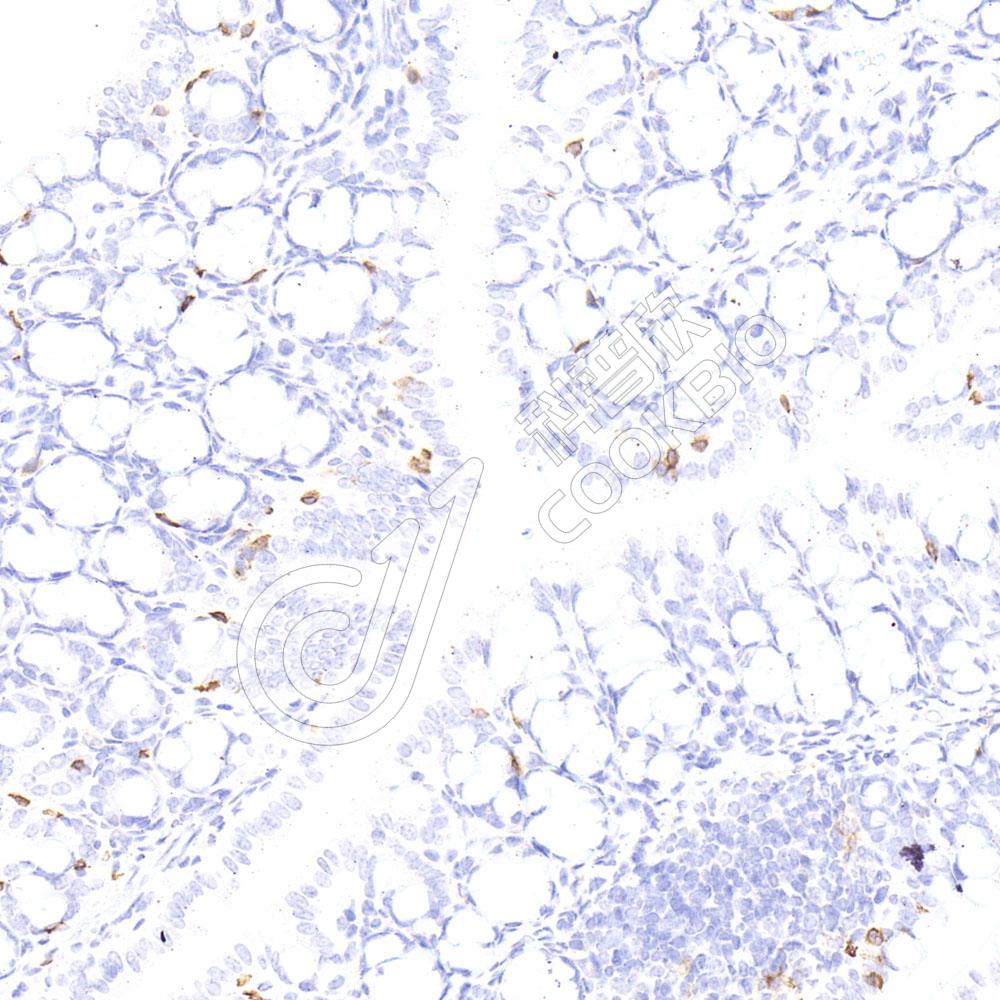

IHC检测PD1蛋白(货号 K5461232).

样品: 小鼠脾, 4%多聚甲醛 (货号KSG1101) 固定12-24小时.

抗原修复: 柠檬酸抗原修复液(干粉, pH 6.0) (KSG1201), 高压锅均匀喷气计时2分钟.

—抗: 1: 300稀释, 4℃ 孵育过夜.

二抗: S-vision免疫组化多聚二抗(山羊抗兔),即用型 (货号KB3906), 室温孵育20分钟.

样品: 小鼠4T1细胞皮下核-M模型, 4%多聚甲醛 (货号KSG1101) 固定12-24小时.